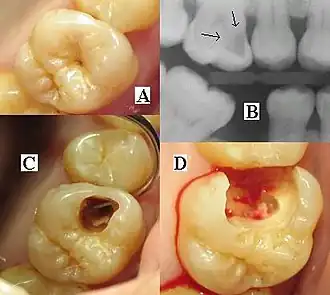

| Destruction of a tooth by dental caries and disease | |

The presentation of caries is highly variable. However, the risk factors and stages of development are similar. Initially, it may appear as a small chalky area (smooth surface caries), which may eventually develop into a large cavitation. Sometimes caries may be directly visible. However, other methods of detection, such as X-rays, are used for less visible areas of teeth and to judge the extent of destruction. Lasers for detecting caries allow detection without ionizing radiation and are now used for the detection of interproximal decay (between the teeth).

Primary diagnosis involves inspection of all visible tooth surfaces using a good light source, dental mirror, and explorer. Dental radiographs (X-rays) may show dental caries before it is otherwise visible, in particular caries between the teeth. Large areas of dental caries are often apparent to the naked eye, but smaller lesions can be difficult to identify. Visual and tactile inspection, along with radiographs, are employed frequently among dentists, in particular to diagnose pit and fissure caries.[89] Early, uncavitated caries is often diagnosed by blowing air across the suspect surface, which removes moisture and changes the optical properties of the unmineralized enamel.

At times, pit and fissure caries may be difficult to detect. Bacteria can penetrate the enamel to reach dentin, but then the outer surface may remineralize, especially if fluoride is present.[91] These caries, sometimes referred to as "hidden caries", will still be visible on X-ray radiographs, but visual examination of the tooth would show the enamel intact or minimally perforated.